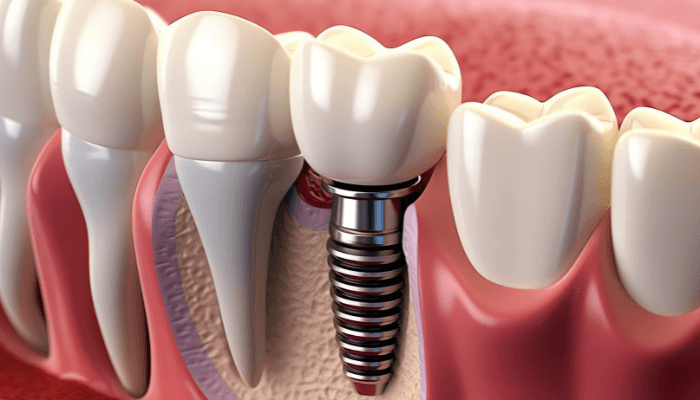

Os implantes dentários são uma solução nova para dentes perdidos. Eles usam um implante de titânio que se une ao osso. Esse processo é chamado de osseointegração.

Os implantes dentários são feitos de titânio. Eles são colocados no osso da mandíbula ou maxila. Isso substitui a raiz de um dente perdido.

Entendendo a osseointegração

A osseointegração é muito importante. Ela faz o implante de titânio se unir ao osso. Isso cria uma base sólida para a prótese dentária.

Esse vínculo entre o implante e o osso é essencial. Ele garante a estabilidade e a funcionalidade do dente artificial.

Implantes de titânio: fortes e duráveis

O implante de titânio é muito usado na cirurgia de dentes. Isso porque ele é biocompatível e tem propriedades mecânicas excepcionais.

Esse material garante a durabilidade e a estabilidade do implante. Assim, oferece uma solução dentária confiável e de alta qualidade.

Os implantes dentários são uma nova forma de colocar dentes. Eles são feitos de titânio e duram muito tempo. Isso acontece porque se fixam bem ao osso da mandíbula.

Durante a cirurgia de colocação do implante, o dentista prepara um local no osso. Esse local é para receber o implante de titânio. Esse processo é chamado de osseointegração. Nesse momento, o implante se une ao osso, criando uma base sólida para a prótese.